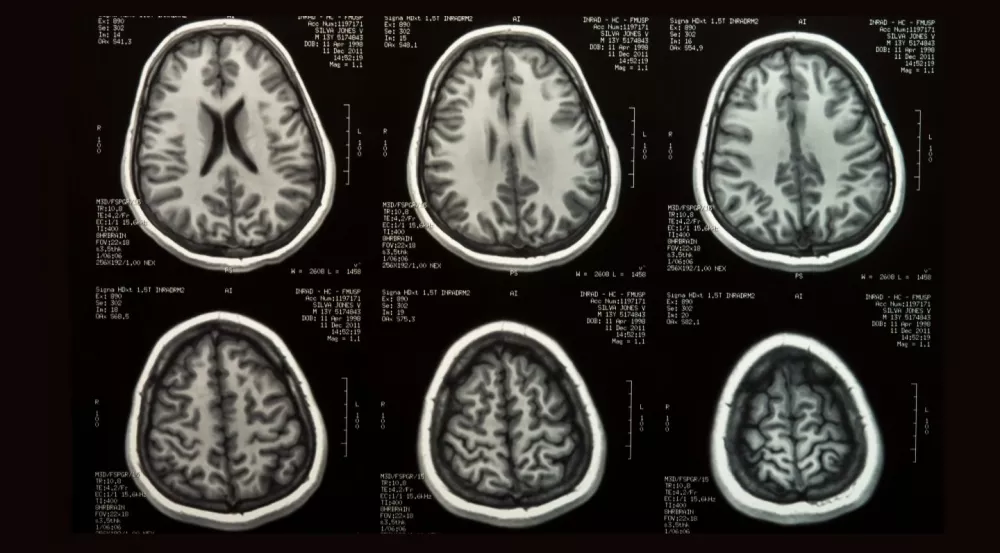

PROCESSAMENTO DE IMAGENS MÉDICAS

PROCESSAMENTO DE IMAGENS MÉDICAS

PROCESSAMENTO DE IMAGENS MÉDICAS

Implementamos soluções avançadas de processamento de imagens para dispositivos médicos e outras industrias, melhorando diagnósticos e operações.

Consulte-nos para mais detalhes.